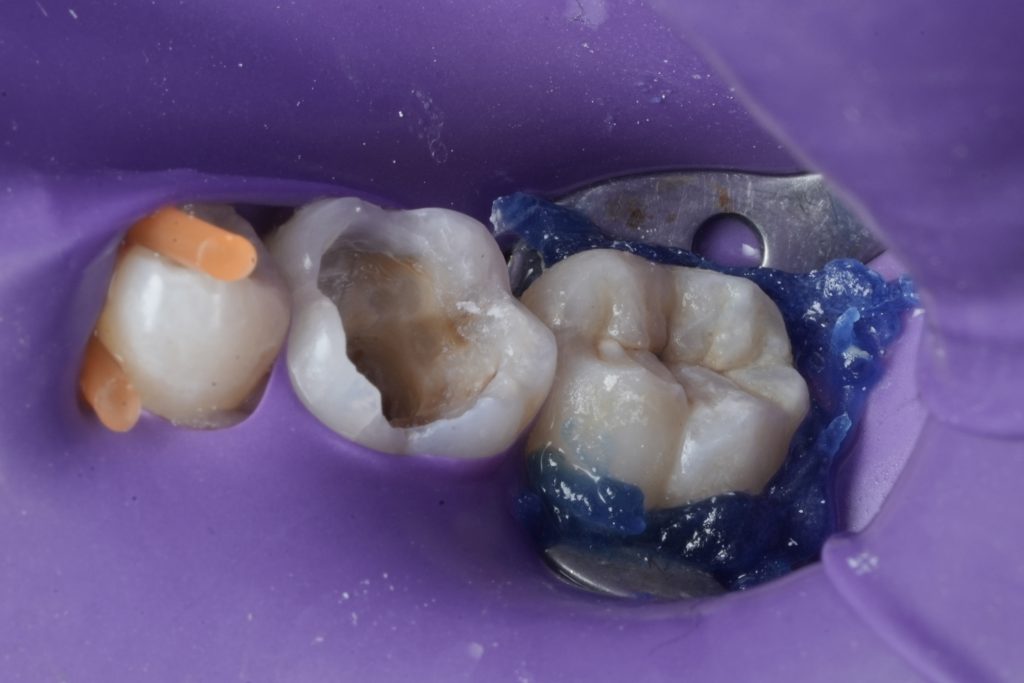

Isolation

Absolute rubber dam isolation was established prior to access preparation. Isolation was maintained throughout both endodontic and restorative phases to ensure a contamination-free environment and optimal bonding conditions.

Access and Canal Management

Conservative access preparation was performed with attention to maintaining pericervical dentin. The canal system was identified and negotiated systematically. Working lengths were established, and patency was confirmed.

Cleaning and shaping were carried out using a controlled, biologically respectful approach, ensuring adequate irrigation and disinfection while preserving canal anatomy.

Core Build-Up

A bonded core build-up was performed under rubber dam isolation. The goal was to:

- Seal the access cavity

- Reinforce weakened walls

- Provide a stable foundation for cuspal coverage